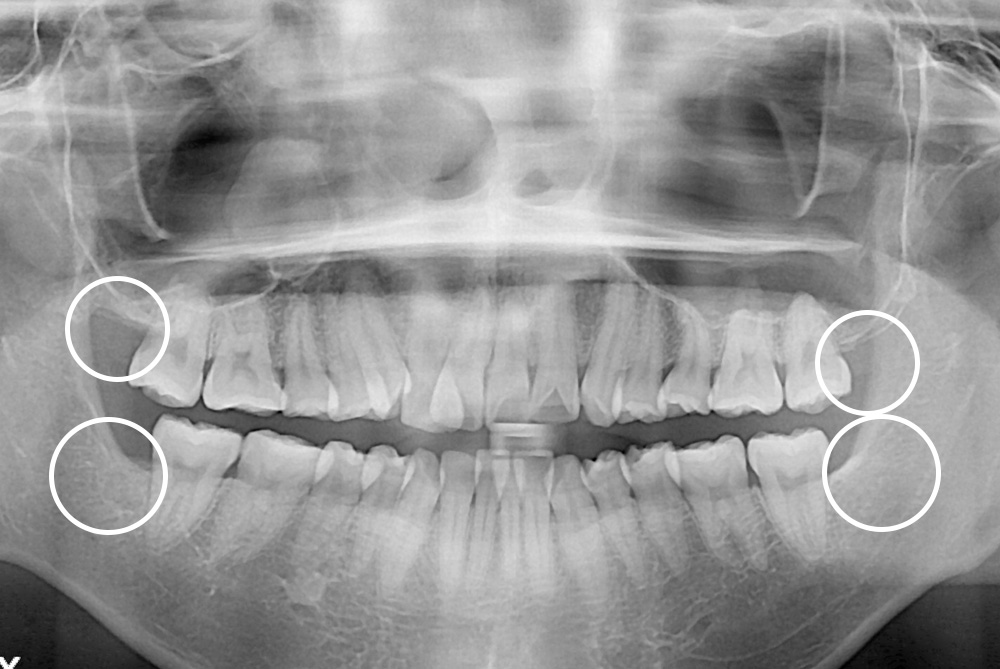

[사랑니] 매복 사랑니 발치

치료전 : 2018-06-18